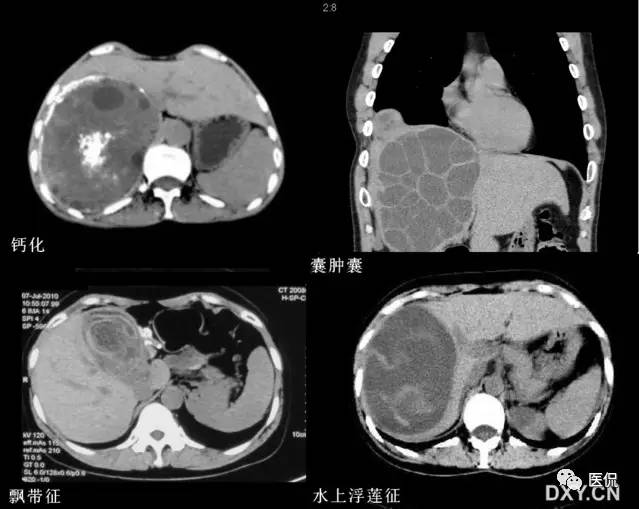

20 囊中囊征又名子囊征

【表现】肝细粒棘球蚴病在B超和CT检查时,母囊内出现大小不一、数目不等的子囊,形成多发或蜂窝状,有时呈车轮状。

【解释】囊中囊征为囊型肝棘球蚴病的特征性表现,母囊即为棘球蚴囊本身,子囊山母囊生发层产生的生发囊或头节。生发囊脱落于囊中,形成子囊,漂浮于母囊中,形成特征性的囊中囊征。

肝棘球蚴病分为两型,山细粒棘球蚴虫卵感染引起的细粒棘球蚴病和山泡状棘球蚴虫卵感染引起的多房棘球蚴病。细粒棘球蚴病约占98%,泡型棘球蚴病少见。两型棘球蝴病的感染途径相同,虫卵被吞食后在小肠内孵出六钩蚴,黝经肠壁血管随血流经门静脉入肝,逐渐发育成肝棘球蚴囊,但其在肝内发生病理改变不同。囊中囊征可见于细粒棘球蚴病。

细粒棘球蚴形成的棘球蚴囊多寄生在肝右叶,常单发,少数多发,呈缓慢膨胀式生长,逐渐长大成巨囊。在生长过程中,棘球蚴囊周围炎症反应形成较厚的纤维性包膜,构成了棘球蚴囊的外囊。棘球蚴囊本身为内囊口外、内囊之问有丰富的血管可保证棘球蚴囊的血供。内囊很薄,山外层的角皮层和内层的生发层组成。角皮层起到保护生发层和吸收营养的作用;生发层有很强的繁殖能力,可向囊腔内生成带细蒂的生发囊,内含许多头节。生发囊脱落于囊中,形成子囊,漂浮于母囊中。头节也可产生子囊。子囊与母囊相同,可继续产生生发囊或孙囊,形成祖孙三代共处一囊中。囊壁破裂为严重的并发症。囊内含有毒性蛋白的液体,可引起变态反应,甚至发生过敏性休克;破裂出的头节种植于腹腔继发新棘球蚴囊。长期生长的棘球蚴囊内囊壁可发生钙化。

细粒棘球蚴病的CT表现颇具特征性,在肝棘球蚴病的诊断,棘球蚴囊肿的定位,了解囊肿数目、大小和形态及并发症方面,CT是一种主要的检查手段。主要表现有:1)单纯囊肿型,肝棘球蚴囊肿大小不一,单发或多发,呈圆形或类圆形,有时呈浅的分叶轮廓,病灶边缘光整、清晰口囊壁密度略高于肝组织,囊壁厚为1~5mm,内外囊壁紧贴,有文献报道,单纯囊肿型可形成双层囊壁结构,显示双壁征。钙化或合并感染时,囊壁明显增厚。囊内密度均匀一致,CT值为-15~25Hu,单纯清澈的囊液密度呈水样,干涸或合并感染时密度升高,注射造影剂后密度不变(无强化)。2)囊内囊,母囊内出现子囊,即囊中囊征,为肝棘球蚴病的特征性表现,文献报道出现率为52. 1%。子囊的数目和大小不一。而且无钙化的子囊密度总是低于母囊,近周边部新生的子囊密度常低于中心部较陈旧的子囊,因而易被CT显示。多个子囊充满母囊时呈多房状或蜂窝状改变,如主要分布在母囊的周边部分则呈车轮状。3)钙化也为常见表现,外囊壁钙化呈弧形或蛋壳状,厚薄可不规则,囊内容物(母囊碎片、退化的头节和子囊)钙化常呈无定形的条片状或片状。4)母囊破裂分离,丙感染、损伤或囊液外漏,可造成内囊分离,有以下几种表现:内、外囊部分分离,CT图像显示为双边征、天幕征;内囊完全分离、塌陷、卷缩并悬浮于囊液中,形成特征性水蛇征、水上浮莲征或水上百合征。偶尔完全分离脱落的内囊撒开呈飘带征。5)并发症以感染最为常见,感染性棘球蚴囊肿有以下特点;囊内密度增高;囊壁增厚;偶见气泡影或形成气-液平面,在排除手术或穿刺术后,被认为是肝棘球蚴囊肿感染的可京征象。此外,因手术或自发破裂后,含头节的囊液流入膜腔内,形成腹腔内棘球蚴囊肿,偶尔可破入胸腔内。

上述各种征象可在同一病例的不同囊内甚至同一囊内见到。CT和B超均为本病的重要检查方法,依据肝棘球蚴病的特征表现囊中囊征等,CT诊断准确率达99%。CT显示各种形态的钙化优于超声,而超声较易发现子囊的壁及囊中碎片等。